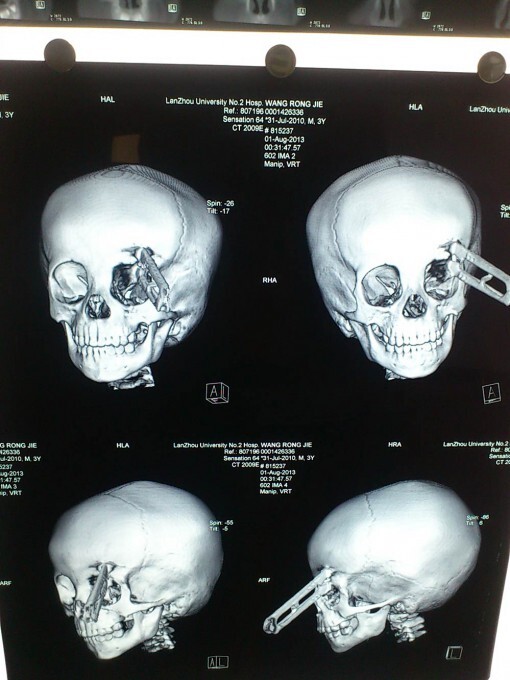

2-летний мальчик чудом выжил после того, как ножницы пронзили его голову в районе глаза. Ван Жиеронг из западной китайской провинции Ганьсу бегал по дому с ножницами, которые он нашел на столе. Неожиданно он споткнулся и упал прямо на ножницы, которые вонзились ему прямо над левым глазом

Мальчика сразу доставили в больницу университета Ланьчжоу в округе Вушань, где врачи провели срочную операцию по удалению ножниц.

Также врачи сообщили, что грязные ножницы могут привести к осложнениям, но малыш, которому всего два года и восемь месяцев уже идет на поправку.